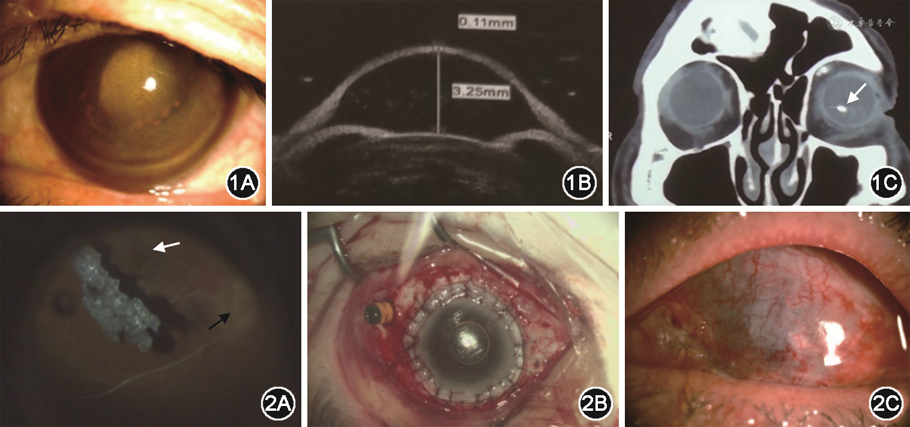

患者男性,58岁。因左眼被铁矿石崩伤后视力下降11个月,于2019年12月就诊于解放军总医院第一医学中心眼科。患者11个月前左眼被铁矿碎屑崩伤后出现眼红、刺痛、流泪。20 d后伤眼视力明显下降伴间断眼痛,根据外院病历记录,主诉为“左眼被石子击伤”。左眼裸眼视力0.4,最佳矫正视力0.7(+1.50 DC×15°),眼压10 mmHg(1 mmHg=0.133 kPa),鼻上方角膜白斑,对应处虹膜脱色素,眼底模糊。视网膜电图:左眼30 Hz闪烁光反应P1波幅降低;a波、b波正常;视觉诱发电位:正常。伤后4个月,左眼裸眼视力降至手动/20 cm,矫正不提高,眼压21 mmHg,角膜透明性差,房水闪光(+)。眼科B超:左眼玻璃体大量点状回声。超声生物显微镜:左眼鼻上方虹膜部分缺如。诊断为左眼外伤性虹膜睫状体炎,抗炎治疗无改善。伤后10个月左眼全角膜灰黄色混浊,菲薄,锥状前突,眼压13 mmHg,眼内结构均窥不见。视网膜电图:左眼a波、b波熄灭;视觉诱发电位:左眼P2波峰潜时明显延迟,波幅显著下降。诊断为左眼角膜血染;左眼继发性圆锥角膜,建议眼球摘除。患者拒绝而转诊至解放军总医院第一医学中心眼科,于门诊自述“左眼被石子击伤”,详问病史得知为铁矿石(赤铁矿)碎屑崩伤。现左眼视物不见伴明显眼痛。既往史、个人史及家族史无特殊。眼部检查:左眼裸眼视力无光感,眼压T+2,左眼结膜轻度混合充血,全角膜菲薄,锥状前突,大量铁锈样物质沉积于角膜基质及内皮面,荧光素染色见角膜上皮散在点染,中央前房深,全周虹膜前粘连,瞳孔直径约5.0 mm,对光反应消失,晶状体黄白色全混,余结构窥不清(图1A)。右眼视力1.0,眼压14 mmHg,前节及眼底未见明显异常。超声生物显微镜显示左眼角膜向前呈钟形膨隆,中央厚度110 μm(图1B)。共聚焦显微镜检查见左眼角膜上皮细胞大小不一、明暗斑驳,未见正常基质细胞及内皮细胞。眼部B超提示异物可能。眼眶CT证实为球内金属异物,大小约5.2 mm×3.3 mm(图1C)。诊断:(1)左眼球内金属异物;(2)左眼继发性圆锥角膜;(3)左眼并发性白内障;(4)左眼继发性青光眼;(5)左眼铁质沉着症。经对症处理,左眼眼压控制在T+1。由于患者拒绝眼球摘除手术,按保留眼球手术计划进行。全身麻醉下行左眼全角膜穿透性角膜移植术、房角分离术、周边虹膜切除术、白内障摘除术、玻璃体切除术、球内异物取出术、硅油填充术和结膜遮盖术。术中剪除全部角膜(直径约10.5 mm)及摘除混浊晶状体后见玻璃体棕褐色点絮状混浊,眼底视盘颜色苍白、边界欠清,黄斑区颜色暗,视网膜菲薄,血管广泛闭塞呈白线状,周边视网膜变性呈大片骨细胞样改变。5∶00方位锯齿缘附近见薄片状不规则灰黑色异物,表面半金属光泽,质地脆,分离异物时其坠入眼底(图2A),异物镊夹出异物后将带巩膜边的全层角膜植片(直径约12.0 mm,刮除全部角膜上皮)间断缝合至植床上(图2B)。玻璃体腔注入硅油,指测眼压Tn;行全结膜遮盖。角膜组织病理学报告:角膜组织厚薄不一,部分上皮缺失,前弹力层消失,基质层纤维组织增生伴玻璃样变性及色素沉着。术后左眼视力无光感,眼压Tn,遮盖的结膜愈合良好(图2C)。